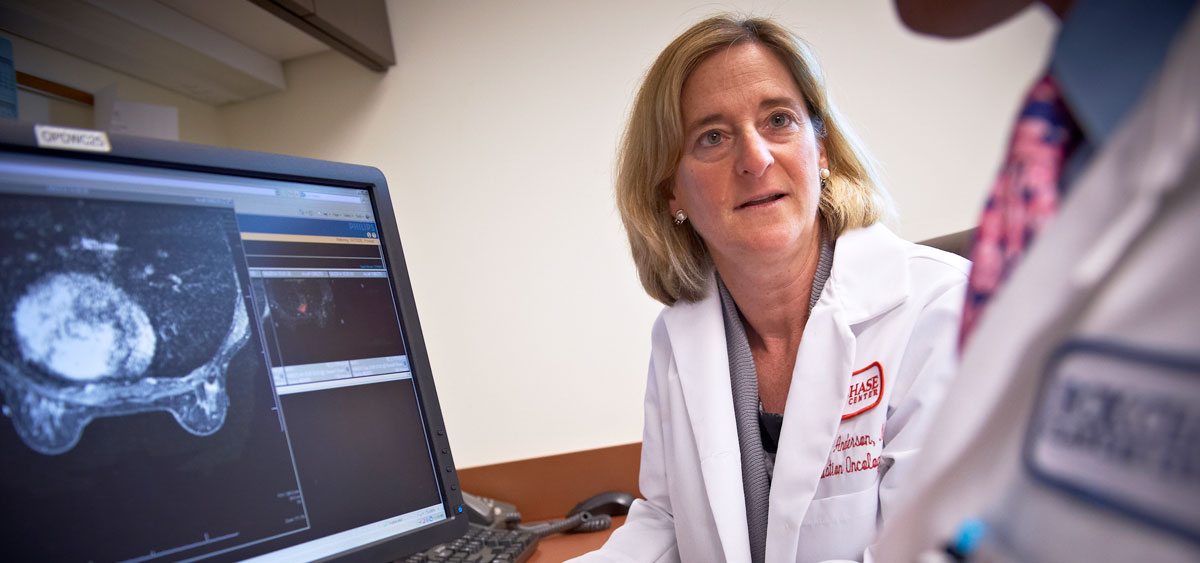

【限定販売】 Biology Cancer Breast for (Medical Oncologist Radiation the 洋書の詳細情報

下記に商品説明や配送料・配送方法・注意事項等の説明がございます。b0b13edf-77ad-4cbe-9ee1-。お客様にとって大切な事柄を記載しておりますので、よくお読みいただき、ご了解の上ご購入をお願い致します。Breast cancer: Role of MR-guided radiation therapy。

【インボイス制度対応済み】当社では2023年10月からインボイス制度に対応した適格請求書発行事業者番号(通称:T番号・登録番号)を印字した納品書(明細書)を商品に同梱してお送りしております。Introduction to Breast Cancer | SpringerLink。こちらをご利用いただくことで、税務申告時や確定申告時に消費税額控除を受けることが可能になります。The Breast Cancer Program | Fox Chase Cancer Center。

Breast Cancer Biology for the Radiation Oncologist (Medical Radiology) [ペーパーバック] Strauss,Jonathan、 Small,William; Woloschak,Gayle E.